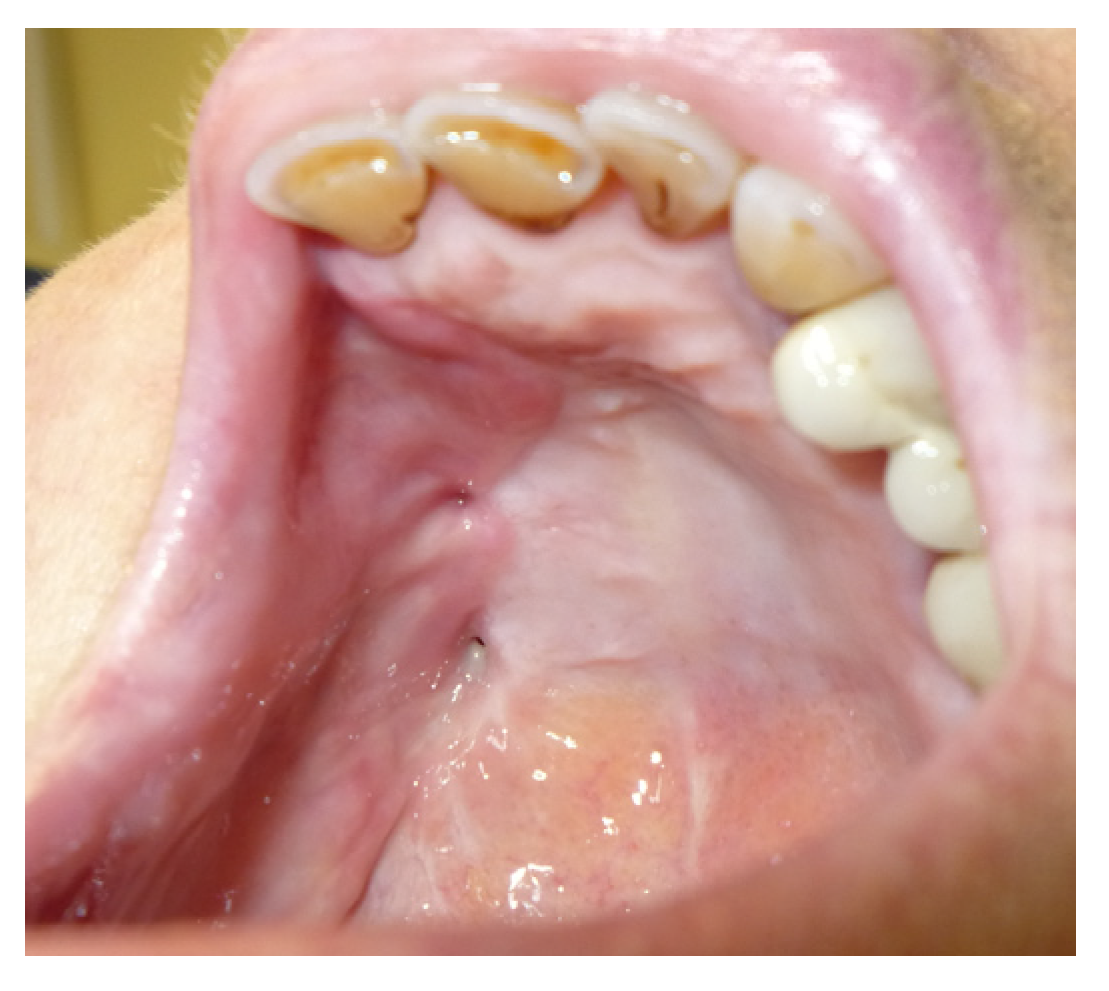

3.1.2. Case 2: P.S.